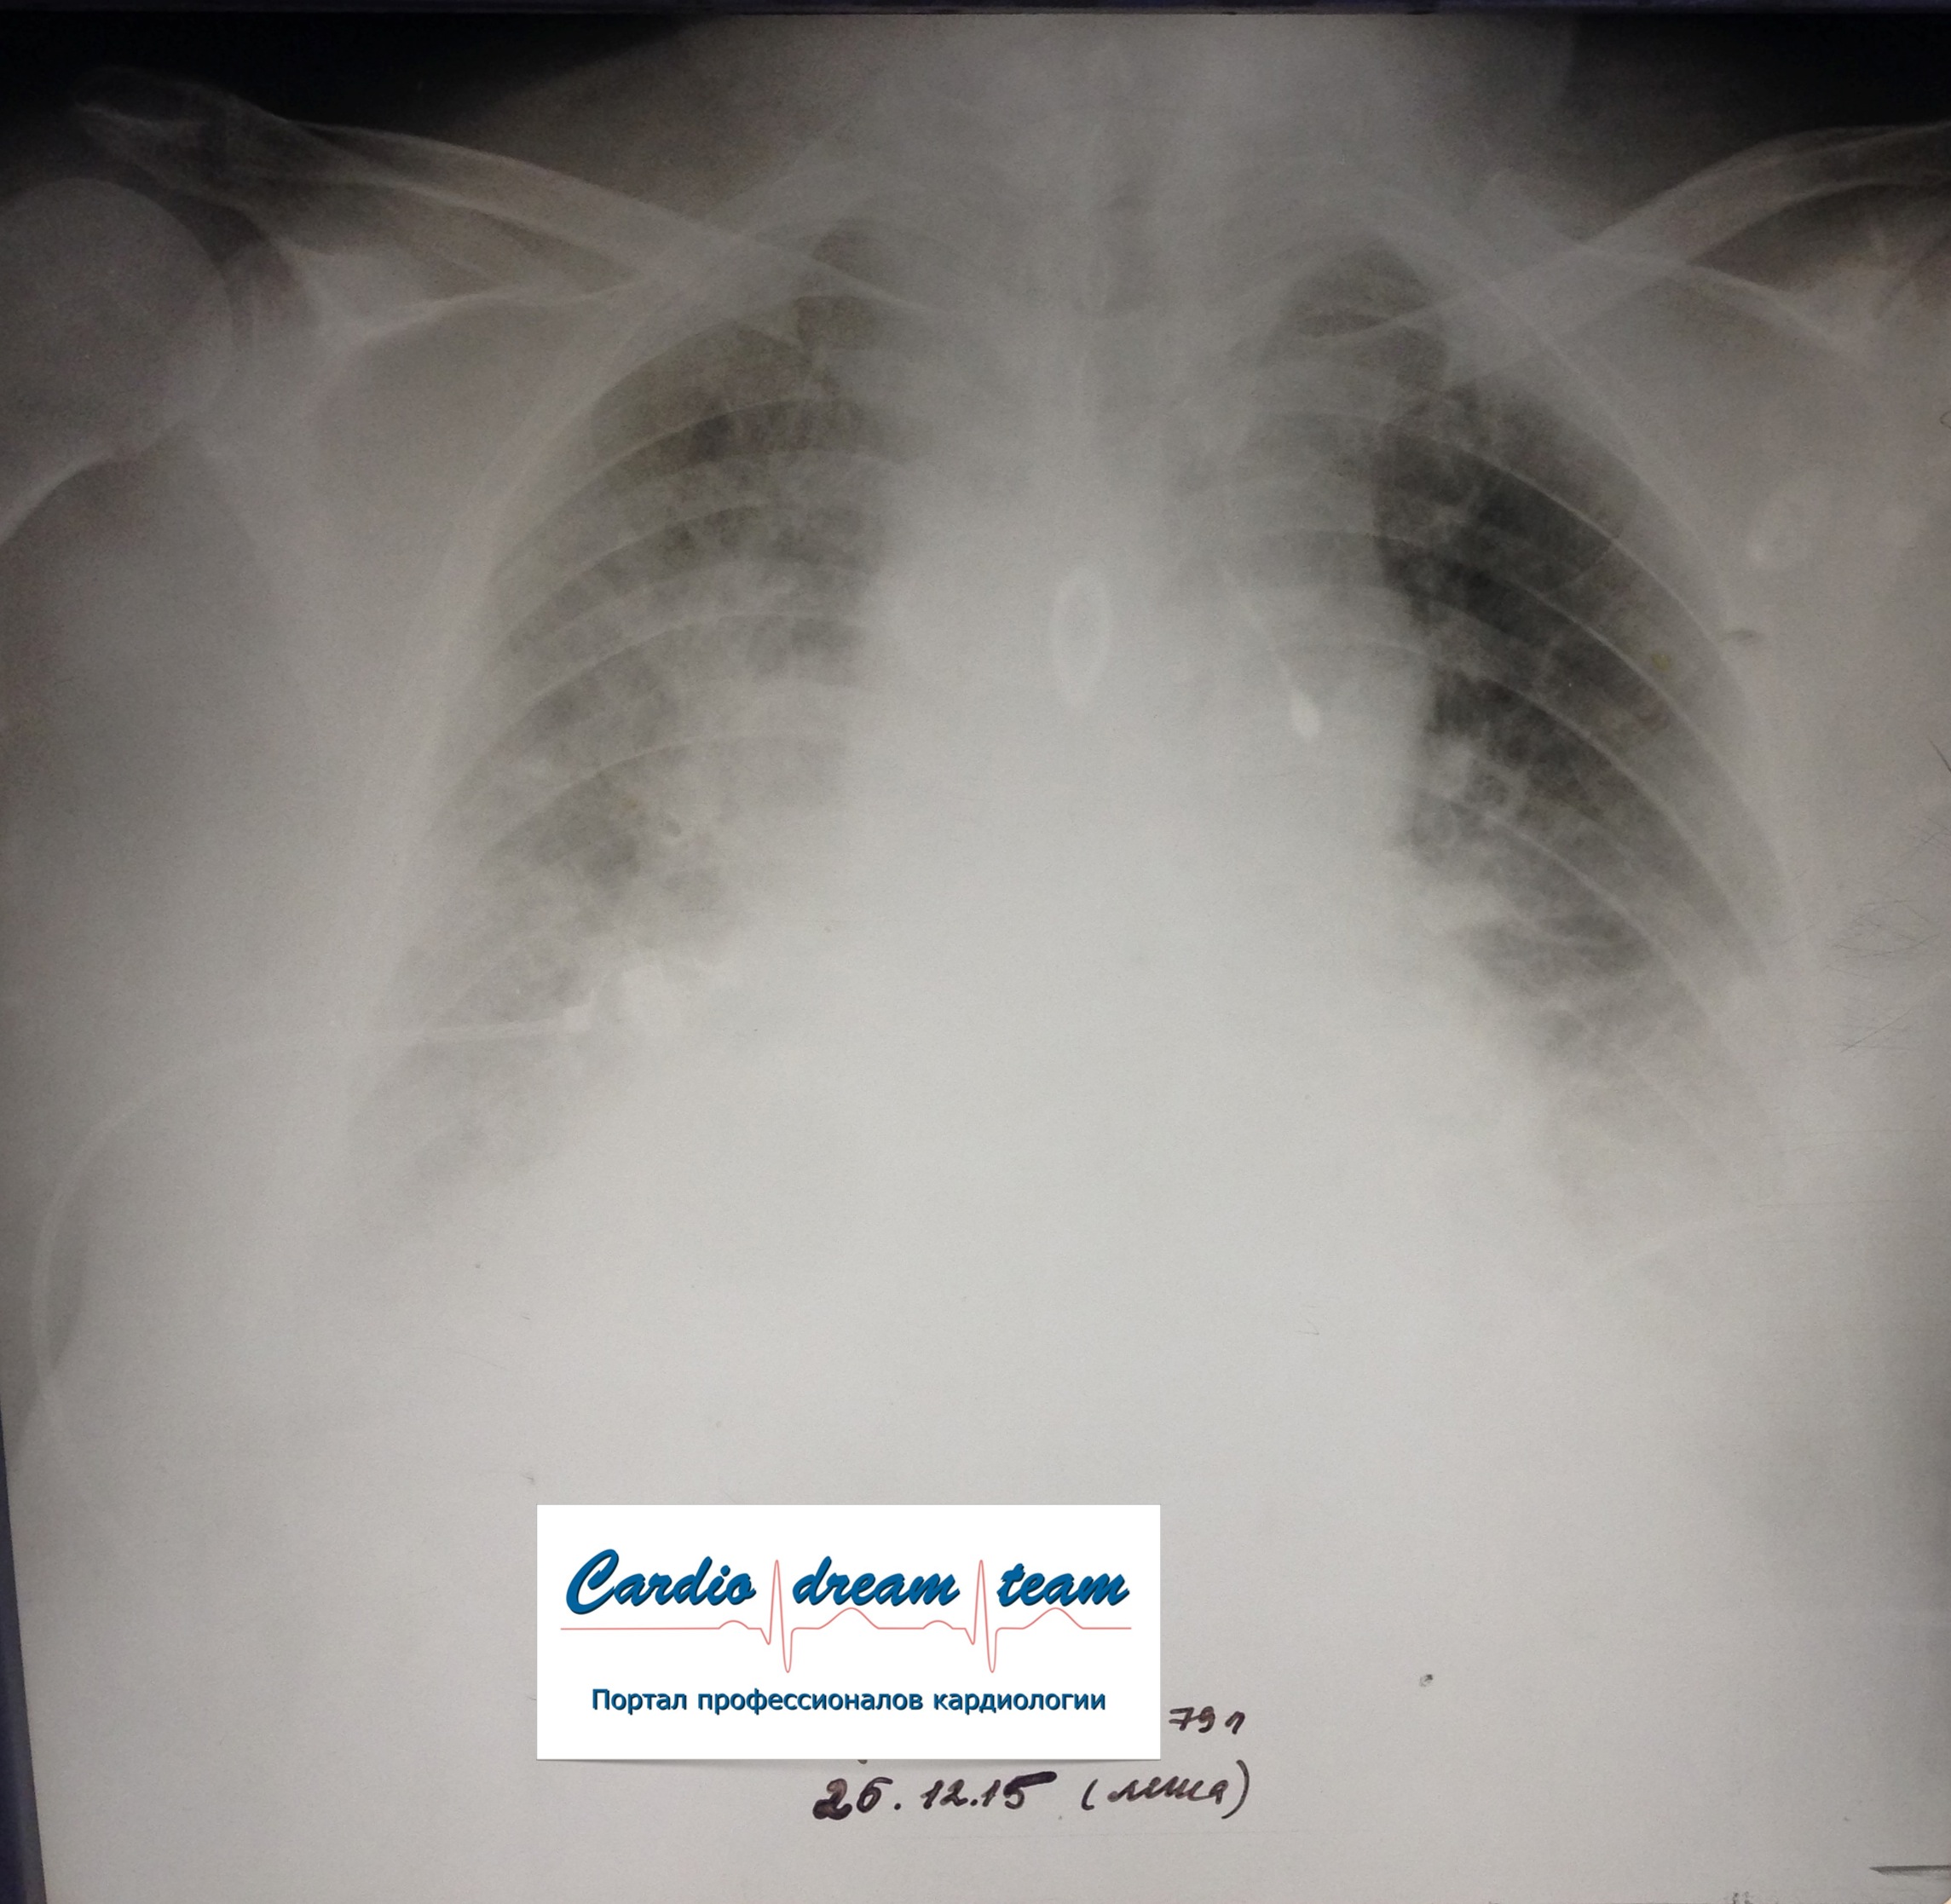

Не обсуждалась Дата 23-ИЮЛ-15 ОПИСАНИЕ: Проведена рентгенография органов грудной клетки в прямой проекции, положение лежа, условия ПИТ Легочные поля: неравномерно прозрачны за счет сосудистого обогащения, в базальных отделах с обеих сторон, отмечается сгущение легочного рисунка, за счет гиповентиляции, в плевральных полостях жидкость Легочный рисунок: Изменен по смешанному типу: обогащен за счет сосудистого компонента, деформирован за счет склероза. Корни: бесструктурны, расширены за счет сосудистого компонента, обогащены Синусы: определяется наличие жидкости по линии 5 ребра Сердце: широко лежит на диафрагме отмечается расширение границ сердечной тени влево, вправо экг-электроды. ЗАКЛЮЧЕНИЕ: Рентген-признаки 2-х стороннего гидроторакса с гиповентиляцией базальных сегментов.. Признаки застоя по МКК 2 степени (умеренно выраженный). Пневмосклероз. Р-признаки гипертрофии левого желудочка сердца. Склероз аорты.